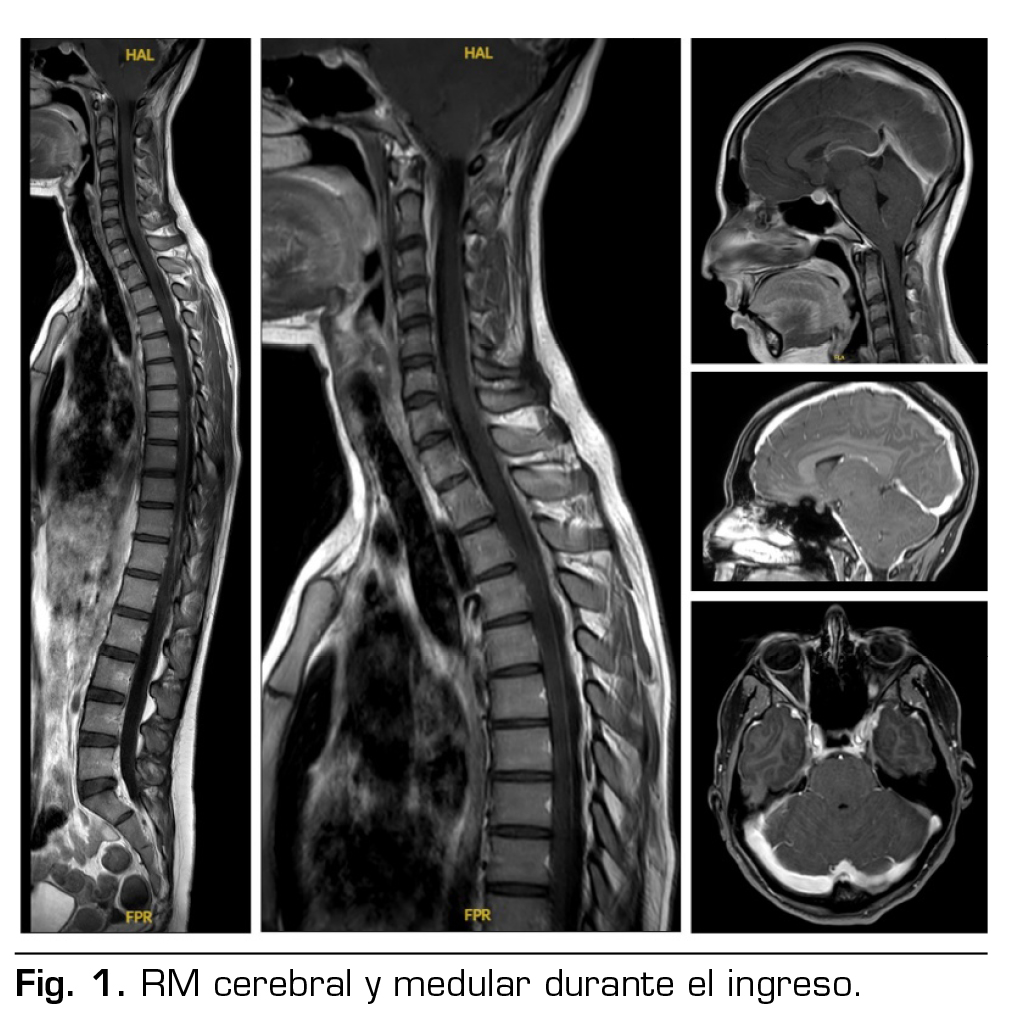

Pruebas complementarias: tomografía computarizada cerebral y analítica normales. RM cerebral y medular: signos de hipotensión intracraneal con engrosamiento dural y pequeñas colecciones laminares en convexidad frontoparietal, colecciones probablemente epidurales en la porción anterior cervical baja y en la región posterior a nivel dorsolumbar (Figura 1).

No se había podido demostrar la existencia de fuga de LCR, pero la presencia de una colección líquida de 57 mm de longitud por delante de la columna anterior del LCR en los segmentos C6-T2, una colección epidural posterior desde T1 hasta T7, y las colecciones en la convexidad frontoparietal, sugerían la localización de las probables fugas, y decidimos realizar un parche hemático no dirigido.

Las tres principales causas y tipos de fuga de LCR en el síndrome de SIH son: desgarro ventral de la duramadre de forma espontánea, a menudo en el contexto de una enfermedad degenerativa de la columna vertebral (tipo I); divertículos meníngeos, que han sido asociados a anomalías del tejido conectivo (tipo II); y fístulas venosas de LCR (tipo III), (2,4,5,6). En cuanto a las pruebas de imagen, podemos caracterizarlas según la localización anatómica: cerebral o medular. Las imágenes cerebrales proporcionan una visión de las secuelas de la pérdida de LCR y son muy útiles para el diagnóstico inicial; el signo más típico es el descenso de las estructuras intracraneanas y un realce paquimeníngeo en la RM. Las imágenes medulares son útiles para buscar el origen de la fuga (5,9,10,11,14). Se han encontrado colecciones extradurales de LCR en aproximadamente la mitad de los pacientes con SIH (2). Las fugas se han localizado más frecuentemente a nivel torácico y cervical (8).